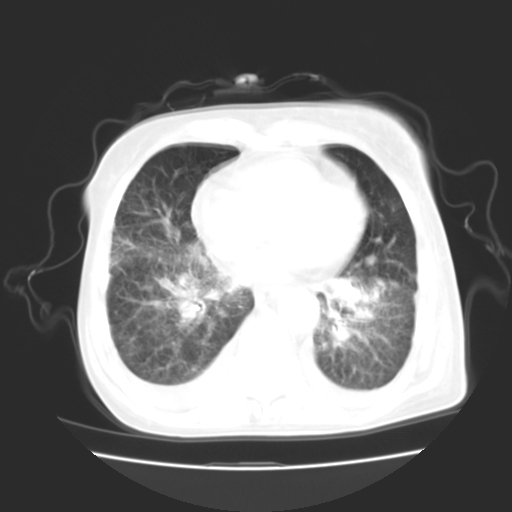

女70y乳腺ca(针吸活检)

1)左侧乳腺癌并左侧腋窝及纵隔淋巴结转移,两肺淋巴道转移(癌性淋巴管炎),肝脏多发性转移。2)双侧胸腔积液。3)慢性胆囊炎。

癌性淋巴管炎,胸膜转移.肝内转移,纵隔及腋窝淋巴结转移

3、双肺癌性淋巴管炎;

4、双侧胸腔积液(考虑淋巴回流障碍所致);

5、肝转移瘤;